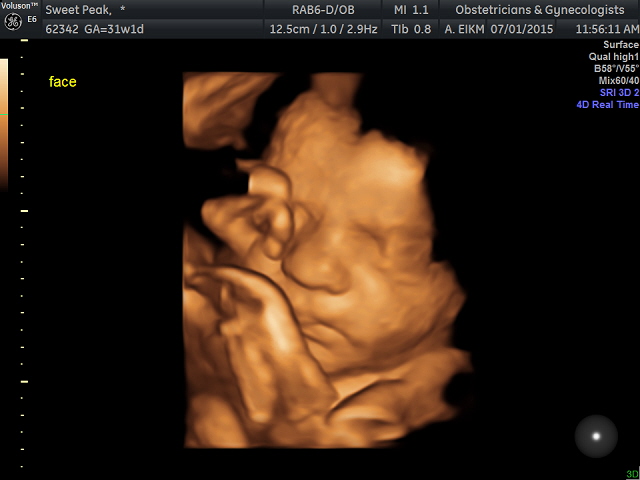

Here are some of mine. I didn't get a good view of his face during the anatomy scan, so I decided to do the elective. My little boy is 31 weeks :)